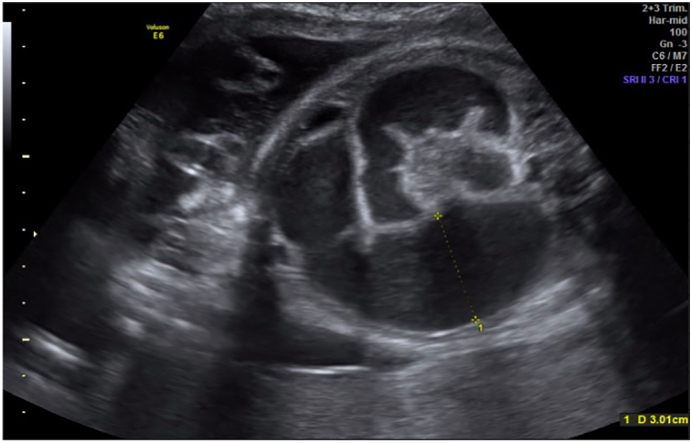

At 26.6 weeks of gestation during prenatal care, obstetric ultrasound showed signs of gastroschisis associated with intestinal atresia, finding intestinal loops in the amniotic cavity with a documented dilation of 17 mm. The mother continued periodic ultrasound control by the perinatology team, showing progressive intestinal dilatation.

During the last prenatal control, the patient presented fetal distress. The ultrasound shows signs of intestinal distress and dilation of 30 mm (Fig. 1). Due to this, the pregnancy was terminated by cesarean section.

Fig. 1.

Intestinal atresia identified by prenatal ultrasonography, showing dilation of intestinal loops of 30 mm and interloop edema.